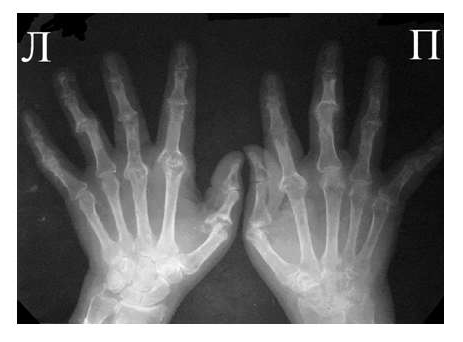

Рис. 5 Множественный остеолиз и деструкции эпифизов костей с разнонаправленными деформациями суставов при псориатическом артрите.

При развернутой картине болезни деструкция концевых фаланг (акроостеолиз) и чашеобразная деформация проксимальной части фаланг пальцев кистей вместе с концевым сужением дистальных эпифизов симптом «карандаш в колпачке» (рис. 5), множественный остеолиз и деструкции эпифизов костей с разнонаправленными деформациями суставов (мутилирующий артрит).